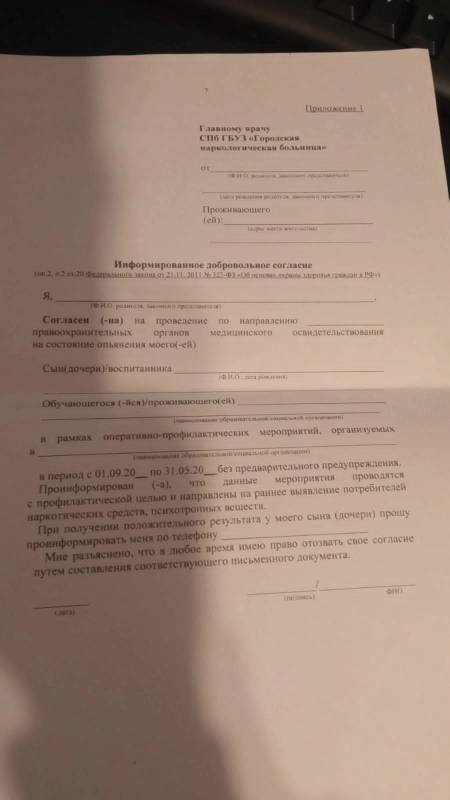

Какое отношение все вышеперечисленное имеет к обычным школьникам? Получается, что в данном случае сотрудники правоохранительных органов должны выписать направление на мед. освидетельствование в отношении несовершеннолетнего по основанию, которое звучит как «на всякий случай» или «просто так», или «почему бы и нет». Это неправовые, абсурдные основания, однако неравнодушные, активные родители прислали нам фото бланка для отказа от подобных мероприятий с разъяснением неких последствий

Такой документ, в силу его правовой неопределенности, мы подписывать не рекомендуем. Для мотивированного и твердого отстаивания своей позиции, мы рекомендуем подать письменный отказ, приведенный на законных основаниях, чтобы избежать риска нелепых претензий и обезопасить своего ребенка от сомнительного мед. вмешательства: